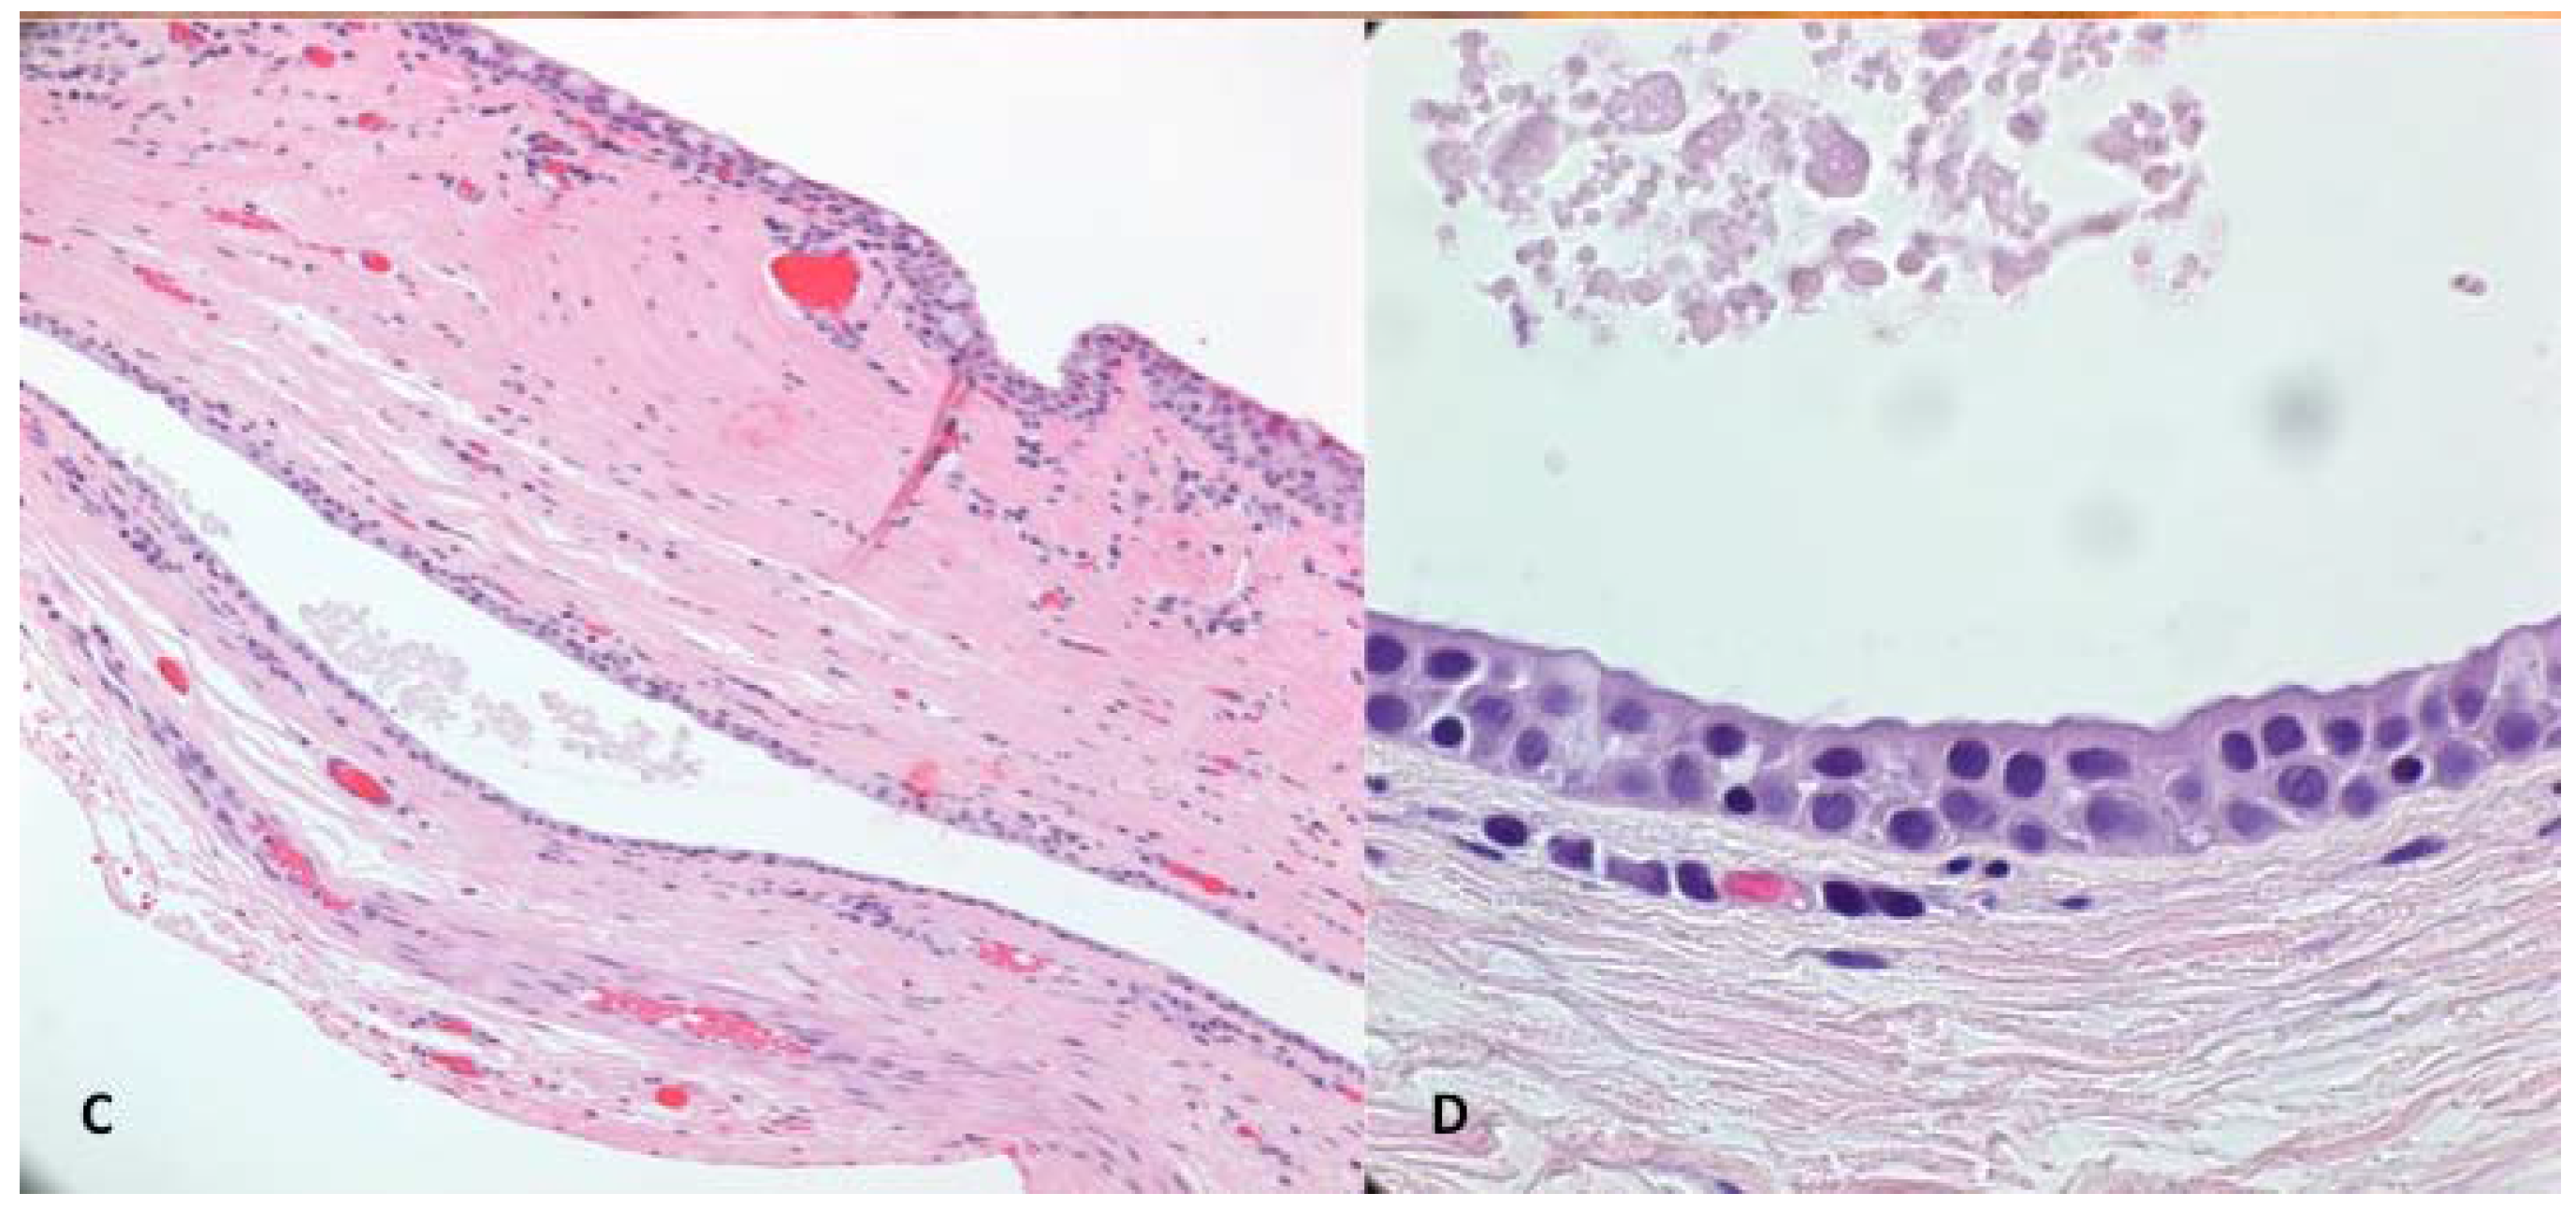

Гистологические изображения фолликулярной кисты яичника